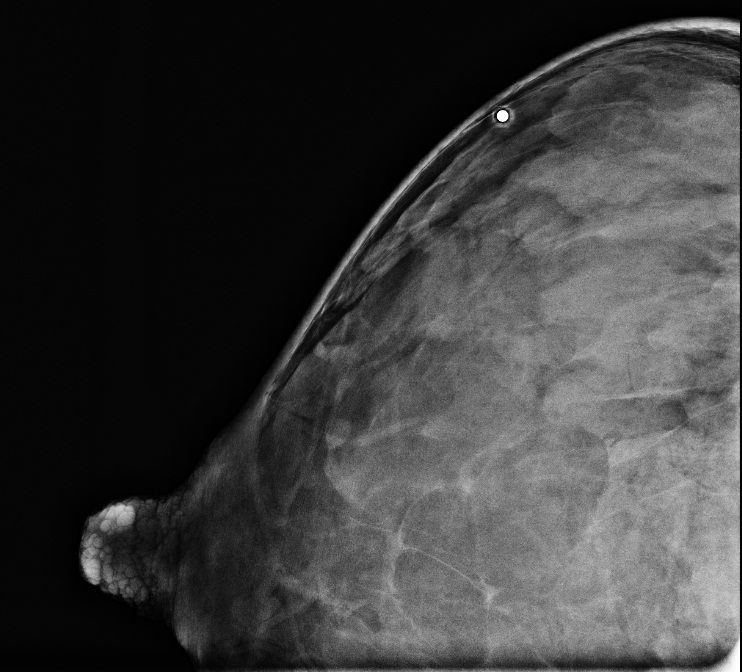

Breast ultrasound finds many cancers missed by mammography, even when reviewed retrospectively.

Breast-specific gamma imaging detects breast cancer in both dense and nondense breast tissue.